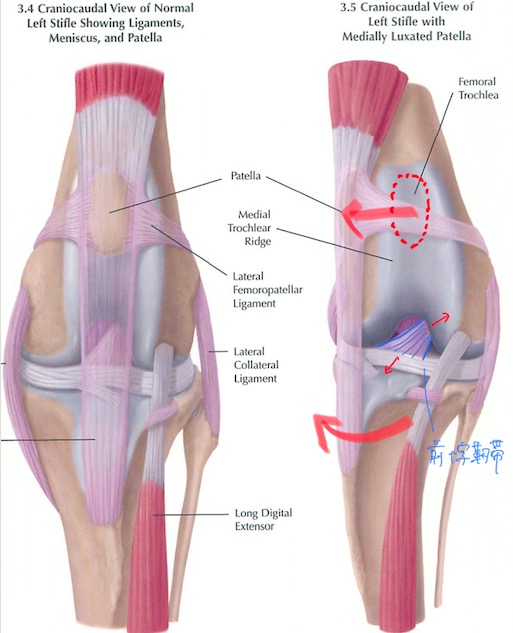

膝蓋骨(パテラ、膝のお皿の骨)の脱臼は犬で最も多く見られる整形外科疾患の1つであり、その多くは生まれ持っての解剖学的な問題による先天性のものです。稀ではありますが猫でも見られます。

日常的に膝蓋骨が脱臼する子は常に膝が内側に引っ張られるような力がかかっており、膝の中にある前十字靭帯に過剰な負荷がかかっていることが多くあります。(赤矢印)

前十字靭帯が損傷すると膝関節が不安定になり、ももの骨とすねの骨が前後にずれるような状態になります。